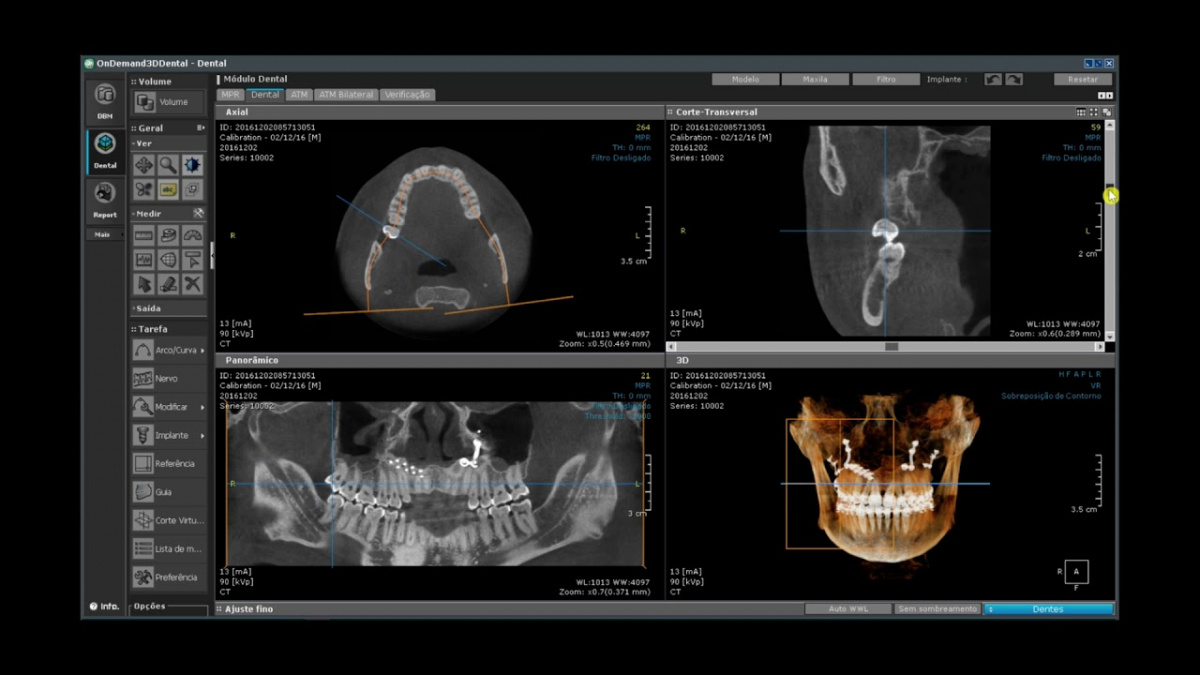

Немаловажным, а может главным вопросом, является универсальность программы-просмотровщика, в которой будут работать врачи-стоматологи. У Papaya 3D есть два варианта программ: Triana и OnDemand3D. Оба просмотровщика обладают схожим интерфейсом и имеют самые важные опции, а именно:

• режим MPR (многоплоскостная реконструкция). Именно здесь выстраивается интересующий участок челюсти или зуба для анализа.

• панорамный реформат. Возможность постройки классической и сегментарной панорамы позволяет продемонстрировать план лечения пациенту, а также оценить расположение анатомических структур на боковых кросс-секциях.

• модуль дентальной имплантации. Возможность виртуальной установки дентального имплантата с анализом окружающей костной ткани. В библиотеке представлен широкий спектр имплантологических систем с индивидуальной прорисовкой имплантата.

• выделение нижнечелюстного канала позволяет продемонстрировать расположение важного анатомического образования и определить зону безопасности при проведении лечения.

• функции плотности, линейных измерений и угла – необходимы для получения полноценной информации для последующего лечения.

• 3D режим – показывает трехмерную модель челюсти с целью определения аномалий, деформация, а также визуализации виртуальных имплантатов.